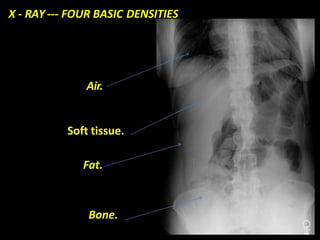

X - RAY --- FOUR BASIC DENSITIES

Air.

Soft tissue.

Fat.

Bone.

X - RAY--- FOUR BASIC DENSITIES Air. Soft tissue. Fat. Bone.